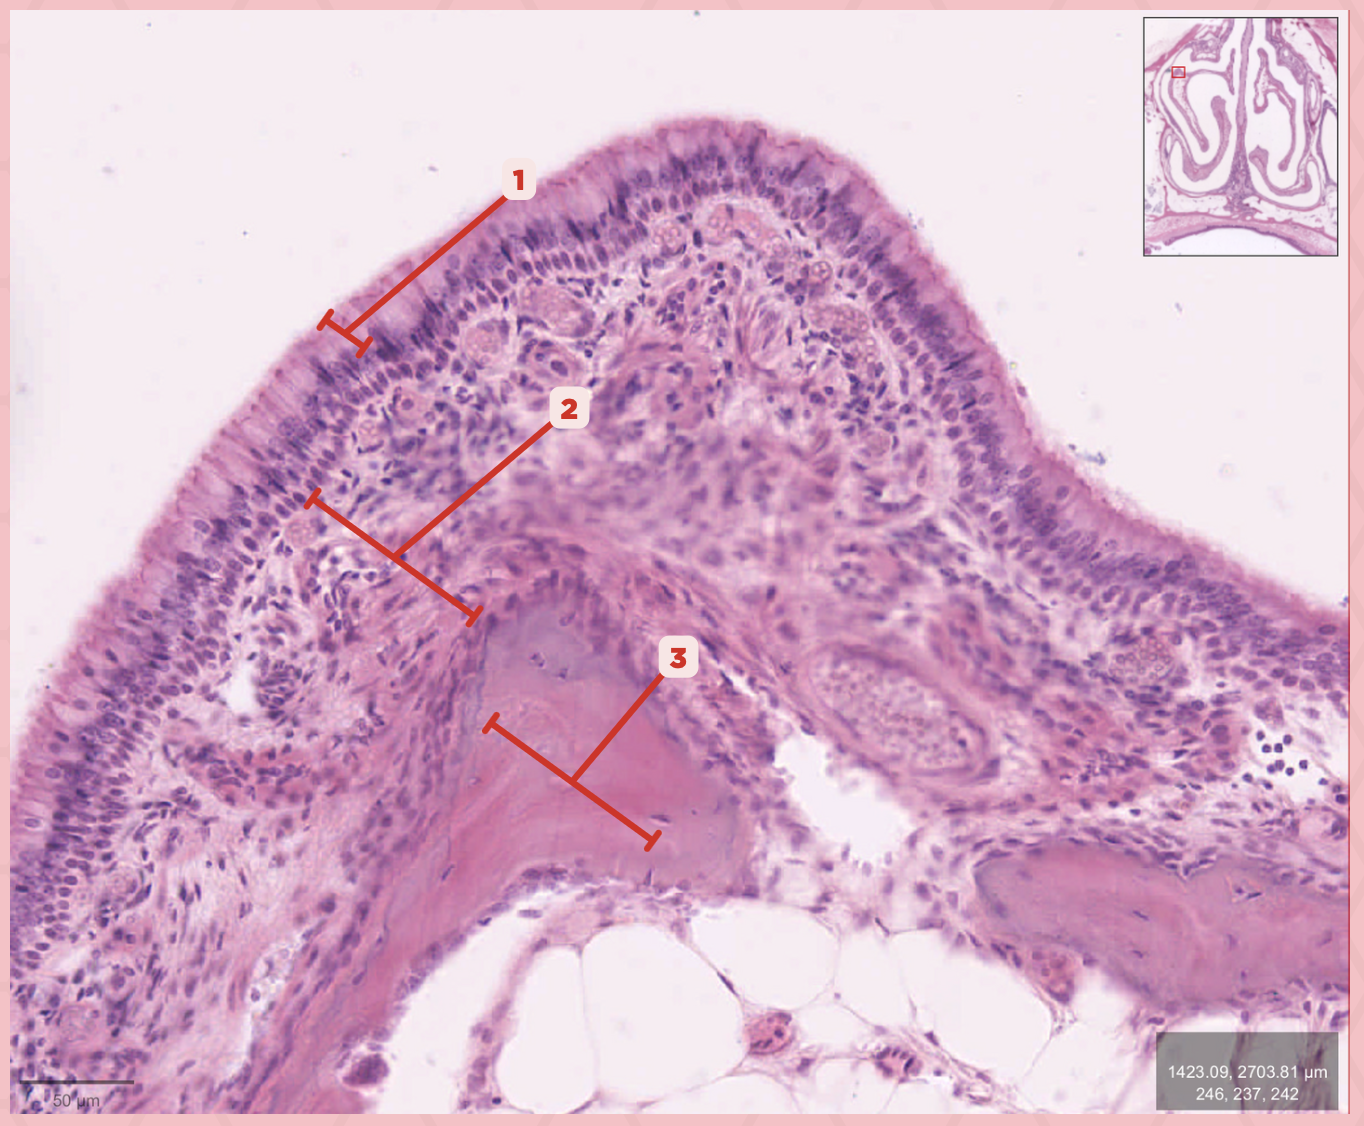

Respiratory Epithelium

Identify the structure labeled as 1.

Lamina Propria

Identify the structure labeled as 2.

Bony spicule

Identify the structure labeled as 3.

Respiratory Epithelium

What epithelium lines this structure?